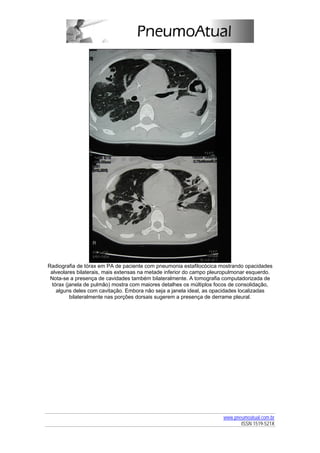

»» Figura 4

Radiografia de tórax em PA

Radiografia de tórax em PA com opacidades intersticiais na base do campo pleuro-pulmonar

esquerdo.